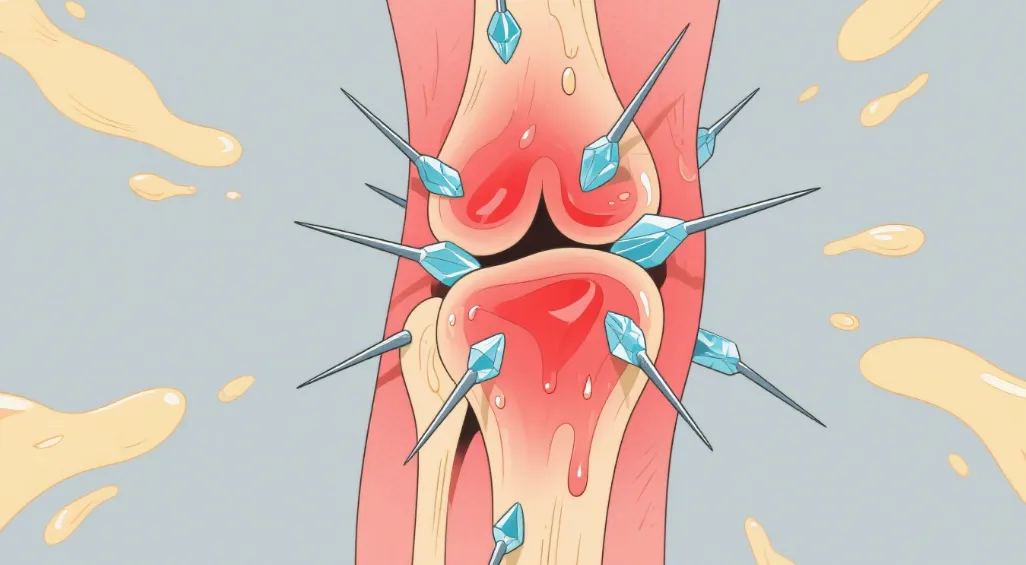

脚趾关节突然刀割样剧痛?半夜被红肿热痛惊醒?这很可能是体内尿酸结晶在作祟!当血尿酸值持续超过420μmol/L,尿酸....【详细】

痛风性关节炎是指尿酸盐结晶沉积发生高尿酸血症,使受累关节引起炎症反应。目前病因及发病机制尚不清楚,可....【详细】